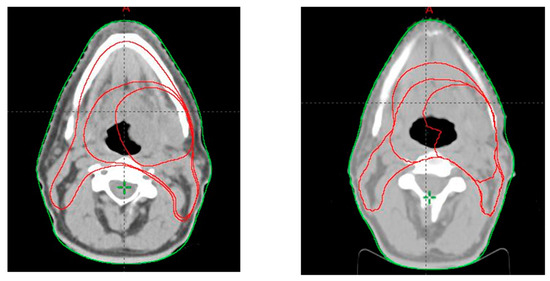

2.2. Target Volume Delineation

3.1. PTV Shrinkage

3.2. Parotid Glands Shrinkage